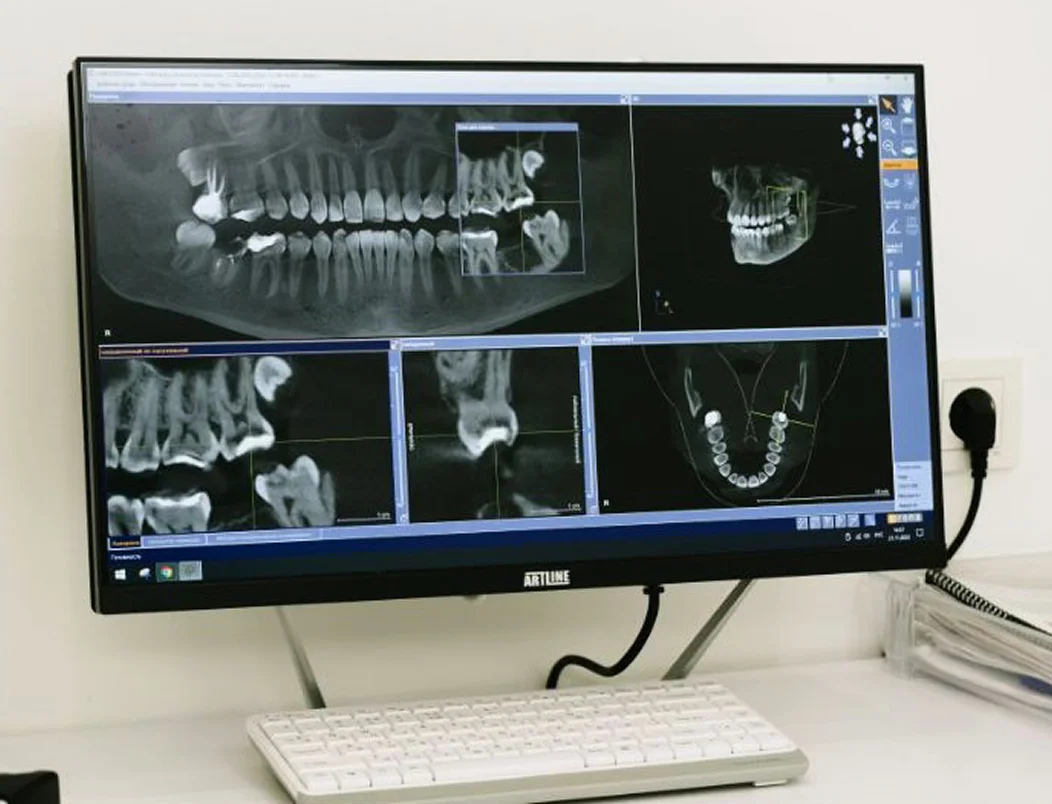

Цифрова діагностика та компʼютерне прогнозування результату

Цифрова діагностика

та компʼютерне прогнозування результату

Обстеження із застосуванням сучасного обладнання — для точного діагнозу та прогнозу подальшого лікування.

Наше кредо — встановлення ПРАВИЛЬНОГО діагнозу з допомогою цифрового обстеження та подальше лікування захворювань за протоколами світової доказової медицини

з допомогою цифрового обстеження та ефективне лікування захворювань за протоколами світової доказової медицини

Для надання професійної медичної допомоги в клініці застосовується сучасне обладнання та цифрові технології.

В ортопедії та ортодонтії – цифрове сканування та комп’ютерне прогнозування результатів лікування.